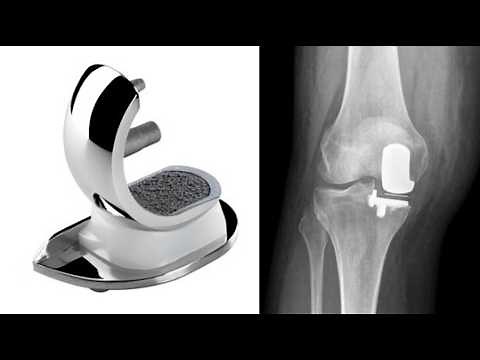

Teilprothese - Homburg

Uniklinik - Teilprothese